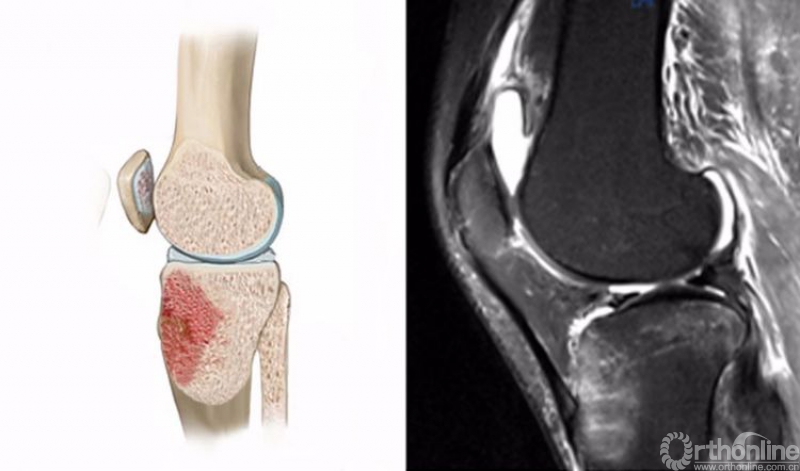

2.仪表板损伤(dashboard injury)

膝关节屈曲时,外力作用于胫骨近端前方,多见于车祸时膝关节撞击前方的仪表盘,也见于跌倒时膝关节撞击地面,是后交叉韧带(PCL)最常见的损伤机制。

膝关节仪表板损伤在MRI上主要表现为胫骨上端前方的骨髓水肿,T2WI及STIR像呈高信号改变,一般预示着PCL损伤。